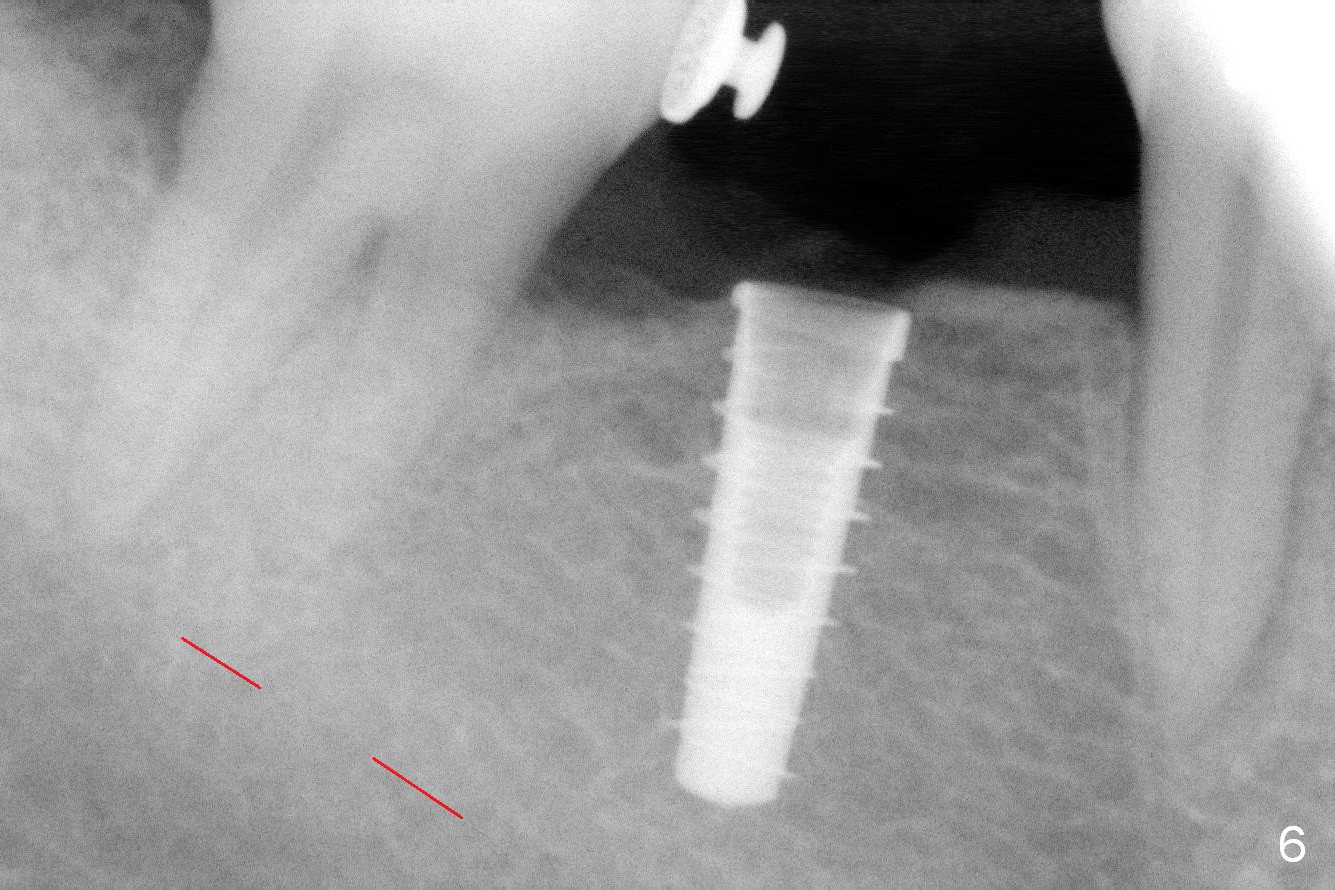

The ridge is found to be fairly narrow after incision. Bone density is determined to be high using #15 blade. A 1.6 mm pilot drill is used to initiate osteotomy (Fig.4). The latter is moved mesially. By the time 3.3 mm Magic Drill is in place, the osteotomy is in the better position mesiodistally (Fig.5). The same is a 4x11 mm IBS implant (Fig.6, >55 Ncm). The lingual button in the mesial of #31 is then removed, because it appears to interfere with placement of a 4.5x4(2) abutment. The position of #31 is maintained by open coil spring.